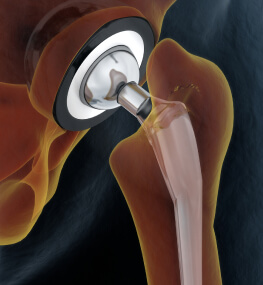

Заміна суглоба - операція не з простих, але сьогодні її роблять настільки часто, що для кваліфікованого лікаря в її проведенні немає нічого складного.

Ендопротезування кульшового суглоба (ціна є в прайсі) відновлює повністю функції нижніх кінцівок і дозволяє людині вільно, без дискомфорту пересуватися. Адже пошкодження тазостегнового суглоба призводить до того, що людина повністю перестає пересуватися через сильний біль.

Операція по заміні суглоба є абсолютно безпечною. При цій процедурі використовується високоякісний протез, який підбирається індивідуально під кожного пацієнта.